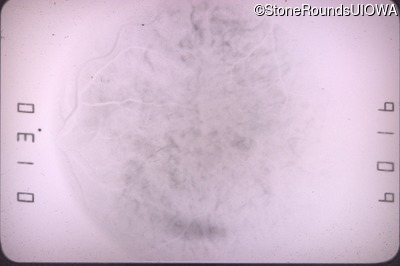

Goldmann Visual Field - Right - 20/20 sc

Exemplar